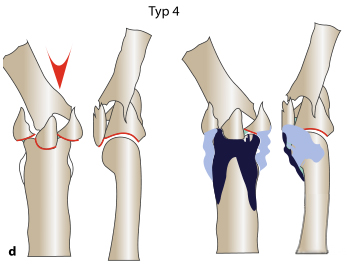

ТИП 4 Перелом распространяется в продольную ось, центральная зона сжатия расширена, наблюдается подвывих и осевое отклонение проксимального межфалангового сустава.